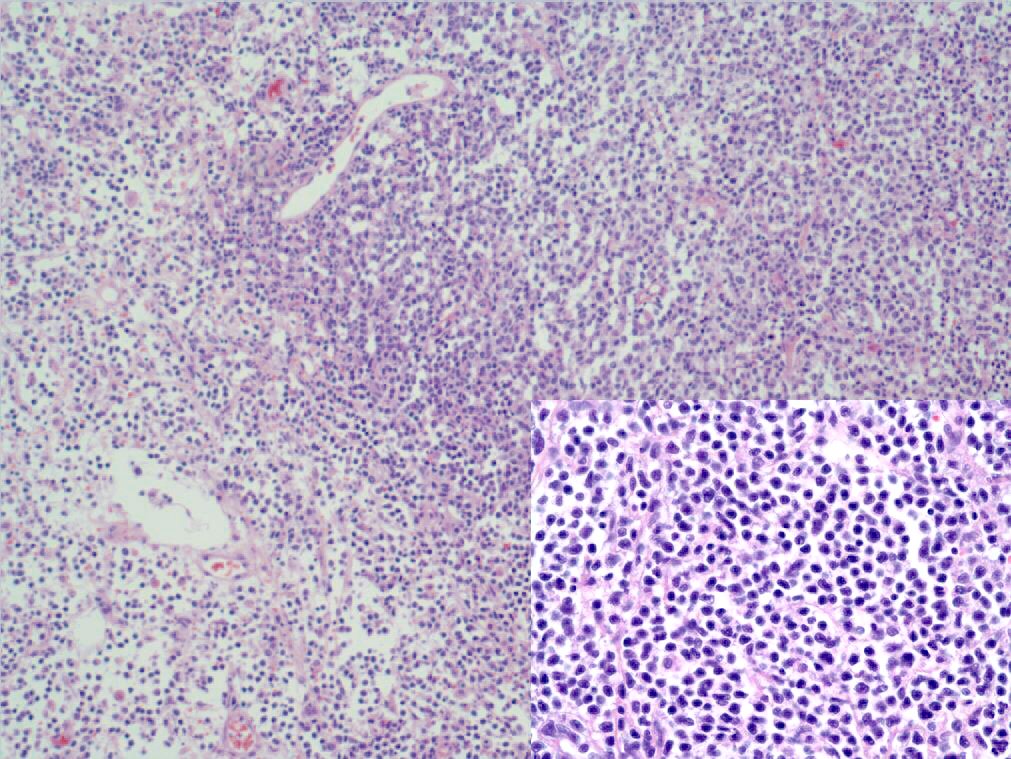

Texas Soc Of Pathol On Twitter What Stains Would You Order On This 5

Bladder Cancer Grading